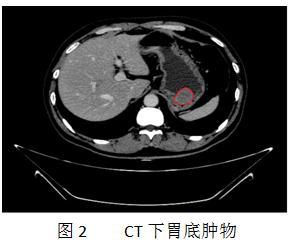

患者入住消化内科后,余细球主任建议完善胸腹部增强CT及超声内镜检查。通过CT检查也看到胃底一直径约4.5cm软组织,高度怀疑肿瘤,万幸的是,周围淋巴结及邻近器官未见转移灶(图2)。